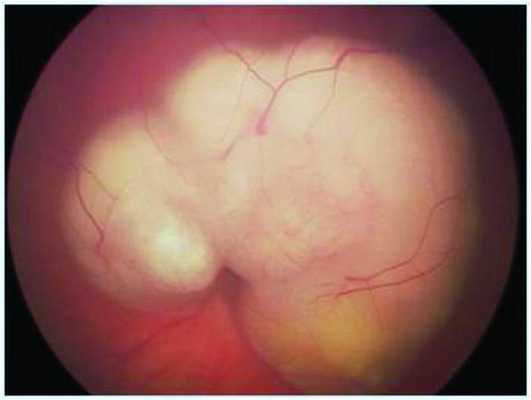

Клинические данные. Мальчик в возрасте 2 лет и 3 мес поступил на обследование и лечение в стационар. Из анамнеза известно, что в возрасте 2 лет родители заметили изменение «окраски» зрачка левого глаза на фотографии, а через 2 мес обратились к врачу по месту жительства, диагноз — подозрение на ретинобластому группы D. До появления первых симптомов ребенка осматривали в 1 год и 7 мес, но без мидриаза. При поступлении острота зрения на левом глазу соответствовала правильной проекции света, передний отрезок глаза без изменений. На глазном дне, по данным осмотра на RetCam, — ДЗН и макула не определяются, прикрыты серо-белой опухолевой тканью с неровными границами и бугристой поверхностью (рис. 1). На правом глазу изменений не выявлено.

Рис. 1. Клиническая картина опухоли при осмотре на RetCam.